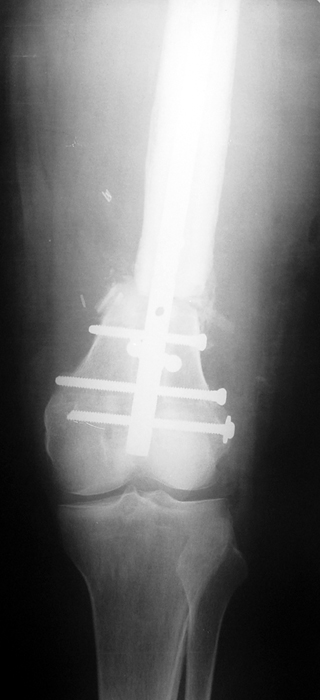

Vaka 1